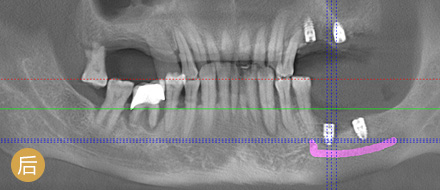

数字化精确导航种植

导航辅助种牙,创口小更舒服

• >智能导航,精确高效

• >适用症广,缺牙重生

• >避免盲种,成功率高

• >种牙精准,不伤神经